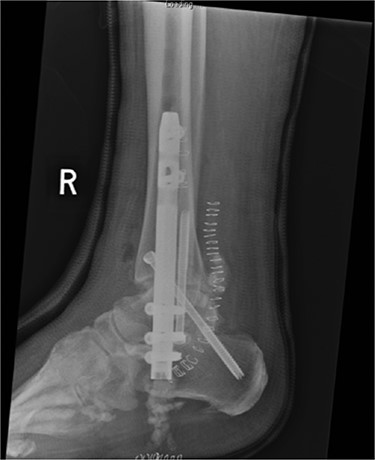

In May 2015, he had a complex midfoot reconstruction, but his foot continued to drift into varus. This was complicated by an infected ulcer on the lateral aspect of midfoot (Fig. 3). Wound infection progressed to osteomyelitis, and in May 2018, he had a hindfoot reconstruction with fusion of tibiotalar and subtalar joints using a Cerament-V-coated hindfoot nail (Figs 4 and 5).

Anterior–posterior radiograph of right ankle demonstrating tibiotalocalcaneal fusion using a hindfoot nail and screws.

Lateral radiograph of right ankle demonstrating tibiotalocalcaneal fusion using a hindfoot nail and screws.